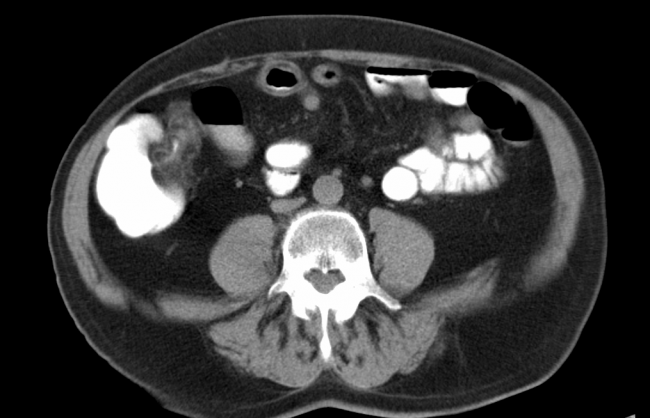

CT-Untersuchungen gehören zu den Klassikern in der Radiologie und sind in der medizinischen Bildgebung nicht mehr wegzudenken. Das CT ist ein klassisches Bildgebungsverfahren, welches unter Verwendung von Röntgenstrahlung präzise Querschnittbilder sämtlicher Körperregionen darstellt. Mögliche Anwendungsbereiche sind z.B.: Frakturen Embolien Infarkten Blutungen Nierensteine Entzündungen Zysten Tumoren und Metastasen Während der Untersuchung werden zwar Röntgenstrahlen freigesetzt, jedoch…